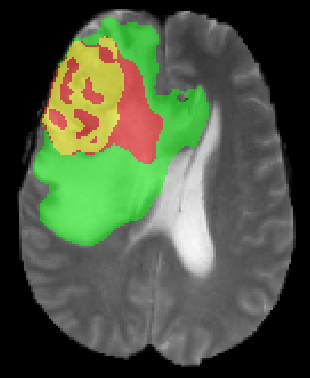

We argue that the sub-optimal paradigm of processing different abstractions within a single CNN pipeline can be remedied through the effective processing of information in a structured manner. Consequently, we devise strategies for disentangling the edge and texture information within a single training pipeline. Figure 2 illustrates how our proposed module, dubbed EG-CNN, can be paired with any existing CNN encoder-decoder to improve segmentation quality near intensity edges. We have applied our EG-CNN to the tasks of brain and liver tumor segmentation in medical images (Figure 3).

(1) Brain MR (2) Liver MR (3) Liver CT (4) Lung CT